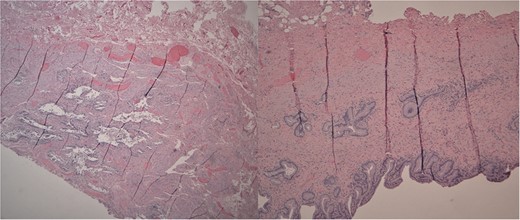

She received normal saline boluses, intravenous piperacillin-tazobactam and vancomycin, and was admitted for sepsis secondary to suspected cholangitis or cholecystitis. Magnetic resonance cholangiopancreatography found no evidence for common bile duct stone, cholecystitis or biliary ductal dilatation. Two blood cultures drawn on admission showed gram-negative rods, so piperacillin-tazobactam was continued. Due to the likelihood of a biliary source for sepsis, laparoscopic cholecystectomy with intraoperative cholangiogram was performed revealing an inflamed gallbladder with multiple stones and no filling defects on cholangiogram (Fig. 3). Gallbladder pathology was consistent with chronic cholecystitis with cholelithiasis and AMH (Fig. 4). The blood cultures and an intraoperative bile culture both grew R. planticola (Fig. 5), which was susceptible to ciprofloxacin. The patient recovered well from her surgery and was discharged home with a 2-week course of oral ciprofloxacin.

Left: Low power H&E of cystically dilated benign biliary glands accompanied by smooth muscle hypertrophy of the gallbladder wall consistent with adenomyomatous hyperplasia. Right: Low power section of fibrotic gallbladder wall with chronic inflammation consistent with chronic cholecystitis.

Macroscopically, the gallbladder was congested with purple discoloration, filled with multiple black bosselated calculi and a 0.7-cm fundic polyp. Microscopy revealed AMH, a reactive nonneoplastic lesion characterized by cystically dilated biliary glands accompanied by smooth muscle hypertrophy of the gallbladder wall. AMH is found in approximately 10% of cholecystectomies [9]. Symptoms of AMH are generally nonspecific. Most patients present with right upper quadrant abdominal pain. Our patient had the fundal variant of AMH, which is most common.